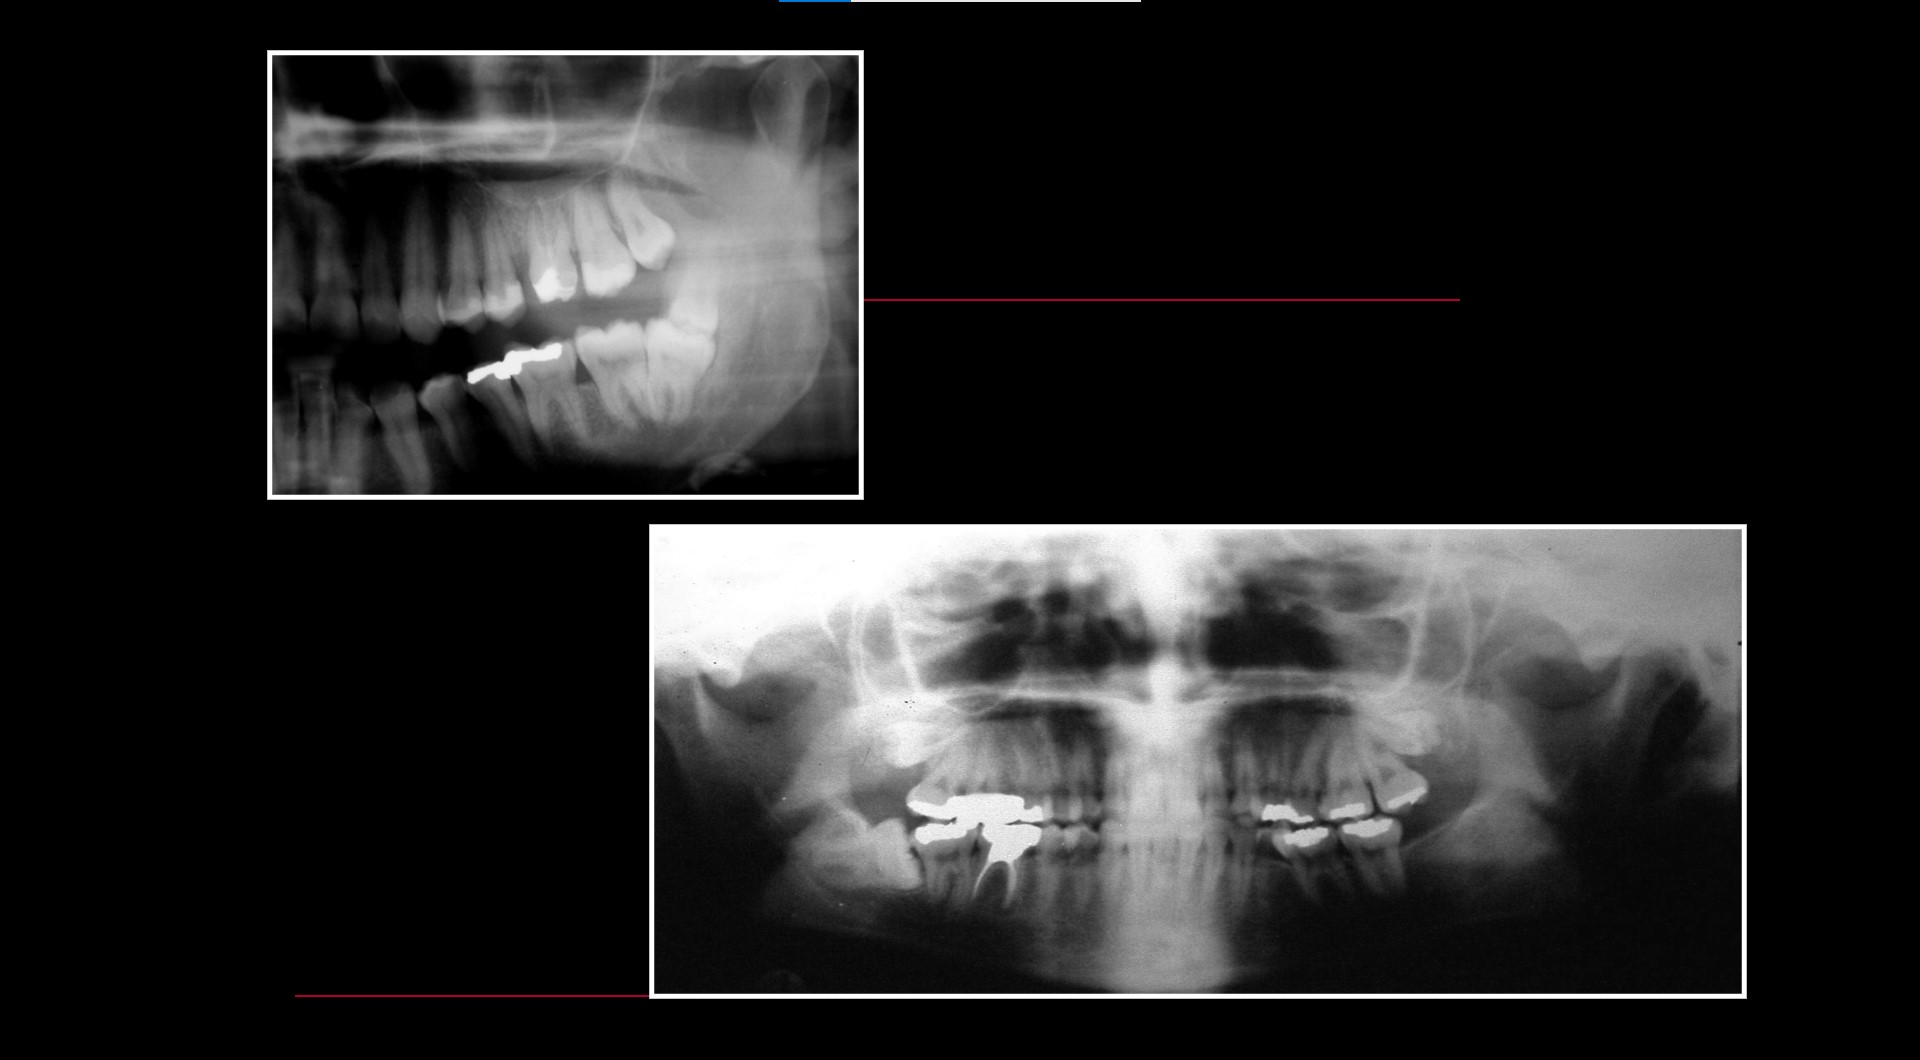

Impacted teeth

Pericoronitis